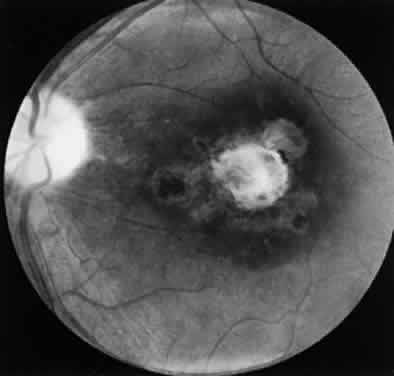

Similar, well-documented cases of retinochoroiditis caused by Toxoplasma after acquired systemic toxoplasmosis have been reported.27,26,51–54 In an outbreak of systemic toxoplasmosis that occurred in October 1977 in Atlanta, Georgia, 37 patients became ill or had serologic evidence of acute infection.22 Epidemiologic studies suggest that infected cats in the riding stable were the source of the infection. Aerosolization of oocysts and hand-to-mouth contact were the presumptive means of transmission. All patients were examined and followed for a year without evidence of Toxoplasma retinochoroiditis. In a 4-year follow-up study, only one patient had shown evidence of ocular disease consisting of an acute retinochoroiditis.27 This suggests that many sporadic cases of acute retinochoroiditis result from or may follow an episode of acquired toxoplasmosis (Fig. 6). Notice that not all cases of retinochoroiditis occur simultaneously with an episode of acquired systemic illness but may manifest any time after the onset of the disease, from a few weeks to years after the acute episode of acquired systemic toxoplasmosis.27 The case described in Figure 6 is one such example.

Fig. 6. Toxoplasma retinochoroiditis after acute systemic toxoplasmosis. A 36-year-old man presented with history of seeing floaters in the right eye of 1 week's duration. The onset of his ocular symptoms occurred 56 days after a flulike illness with postauricular lymphadenopathy. Acute and convalescent serum specimens were obtained and showed an increase in Toxoplasma antibody titers from negative to 1:1024. A. Single focus of retinochoroiditis below the macular area of the right eye (vision: 20/200 [metric equivalent 6/60]). The left eye was normal with 20/20 (6/6) vision. B. Fluorescein angiography (early late phase) indicates leakage from retinal capillaries. C. Two months after a 3-week course of clindamycin, sulfadiazine, and systemic corticosteroids, the lesion completely resolved. The patient's vision decreased because of epiretinal gliotic membrane formation, causing macular pucker and subretinal neovascularization.